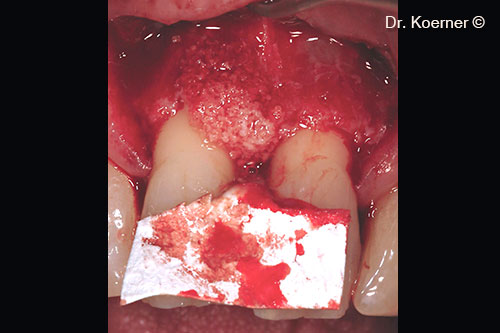

Incision following the Modified Papilla Preservation Technique

Root planning with Piezo diamond tip

Defect filled with mp3® and tailored Evolution membrane